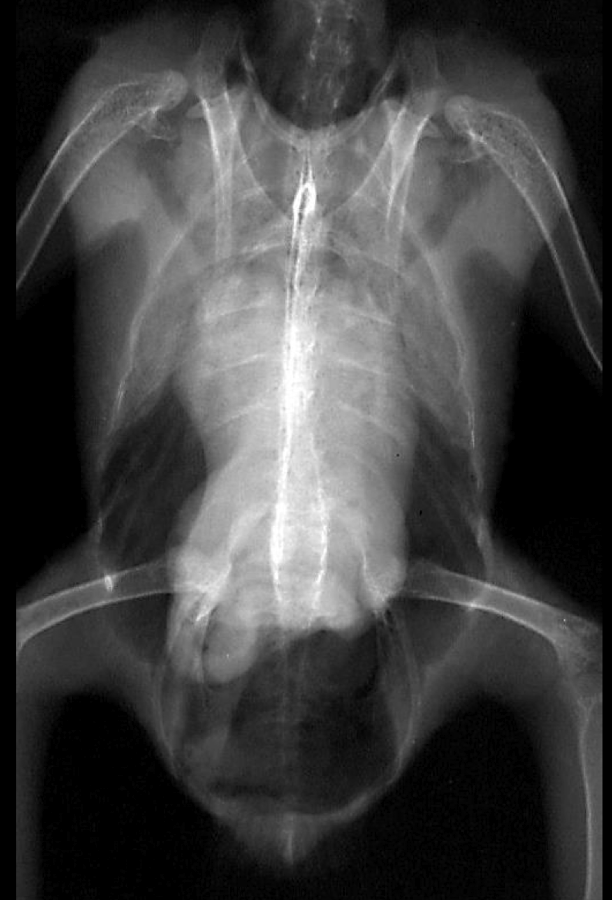

Normal avian body xray

Normal avian lateral xray